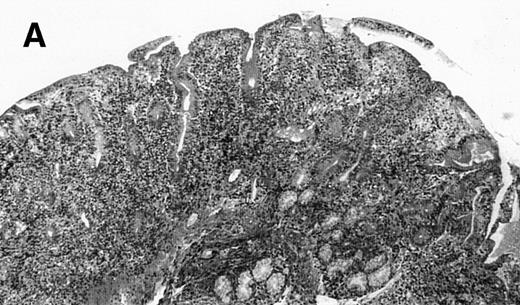

(A) Case no. 1. (B and C) Case no. 2. (D) Case no. 3. (E) Case no. 4. (A, B, D, and E) Duodenal biopsies showing total villous atrophy with crypt hyperplasia and infiltration of lamina propria by nonatypical inflammatory cells (Hematoxylinandeosin; original magnification × 10). (C) Jejunal biopsy showing villous atrophy and ulcerations with regenerative epithelial changes on the border of ulcerations; no evidence of lymphoma.

The 4 patients with complicated CD had duodenal biopsies consistent with untreated CD; total villous atrophy, intraepithelial lymphocytosis, crypt hypertrophy, and inflammation of lamina propria with benign-appearing lymphocytes, plasma cells, and eosinophils were observed. There was no histological evidence of lymphoma. Patient no. 4 also had biopsies performed at the border of duodenal ulcerations that showed epithelial erosions without histological evidence of lymphoma.